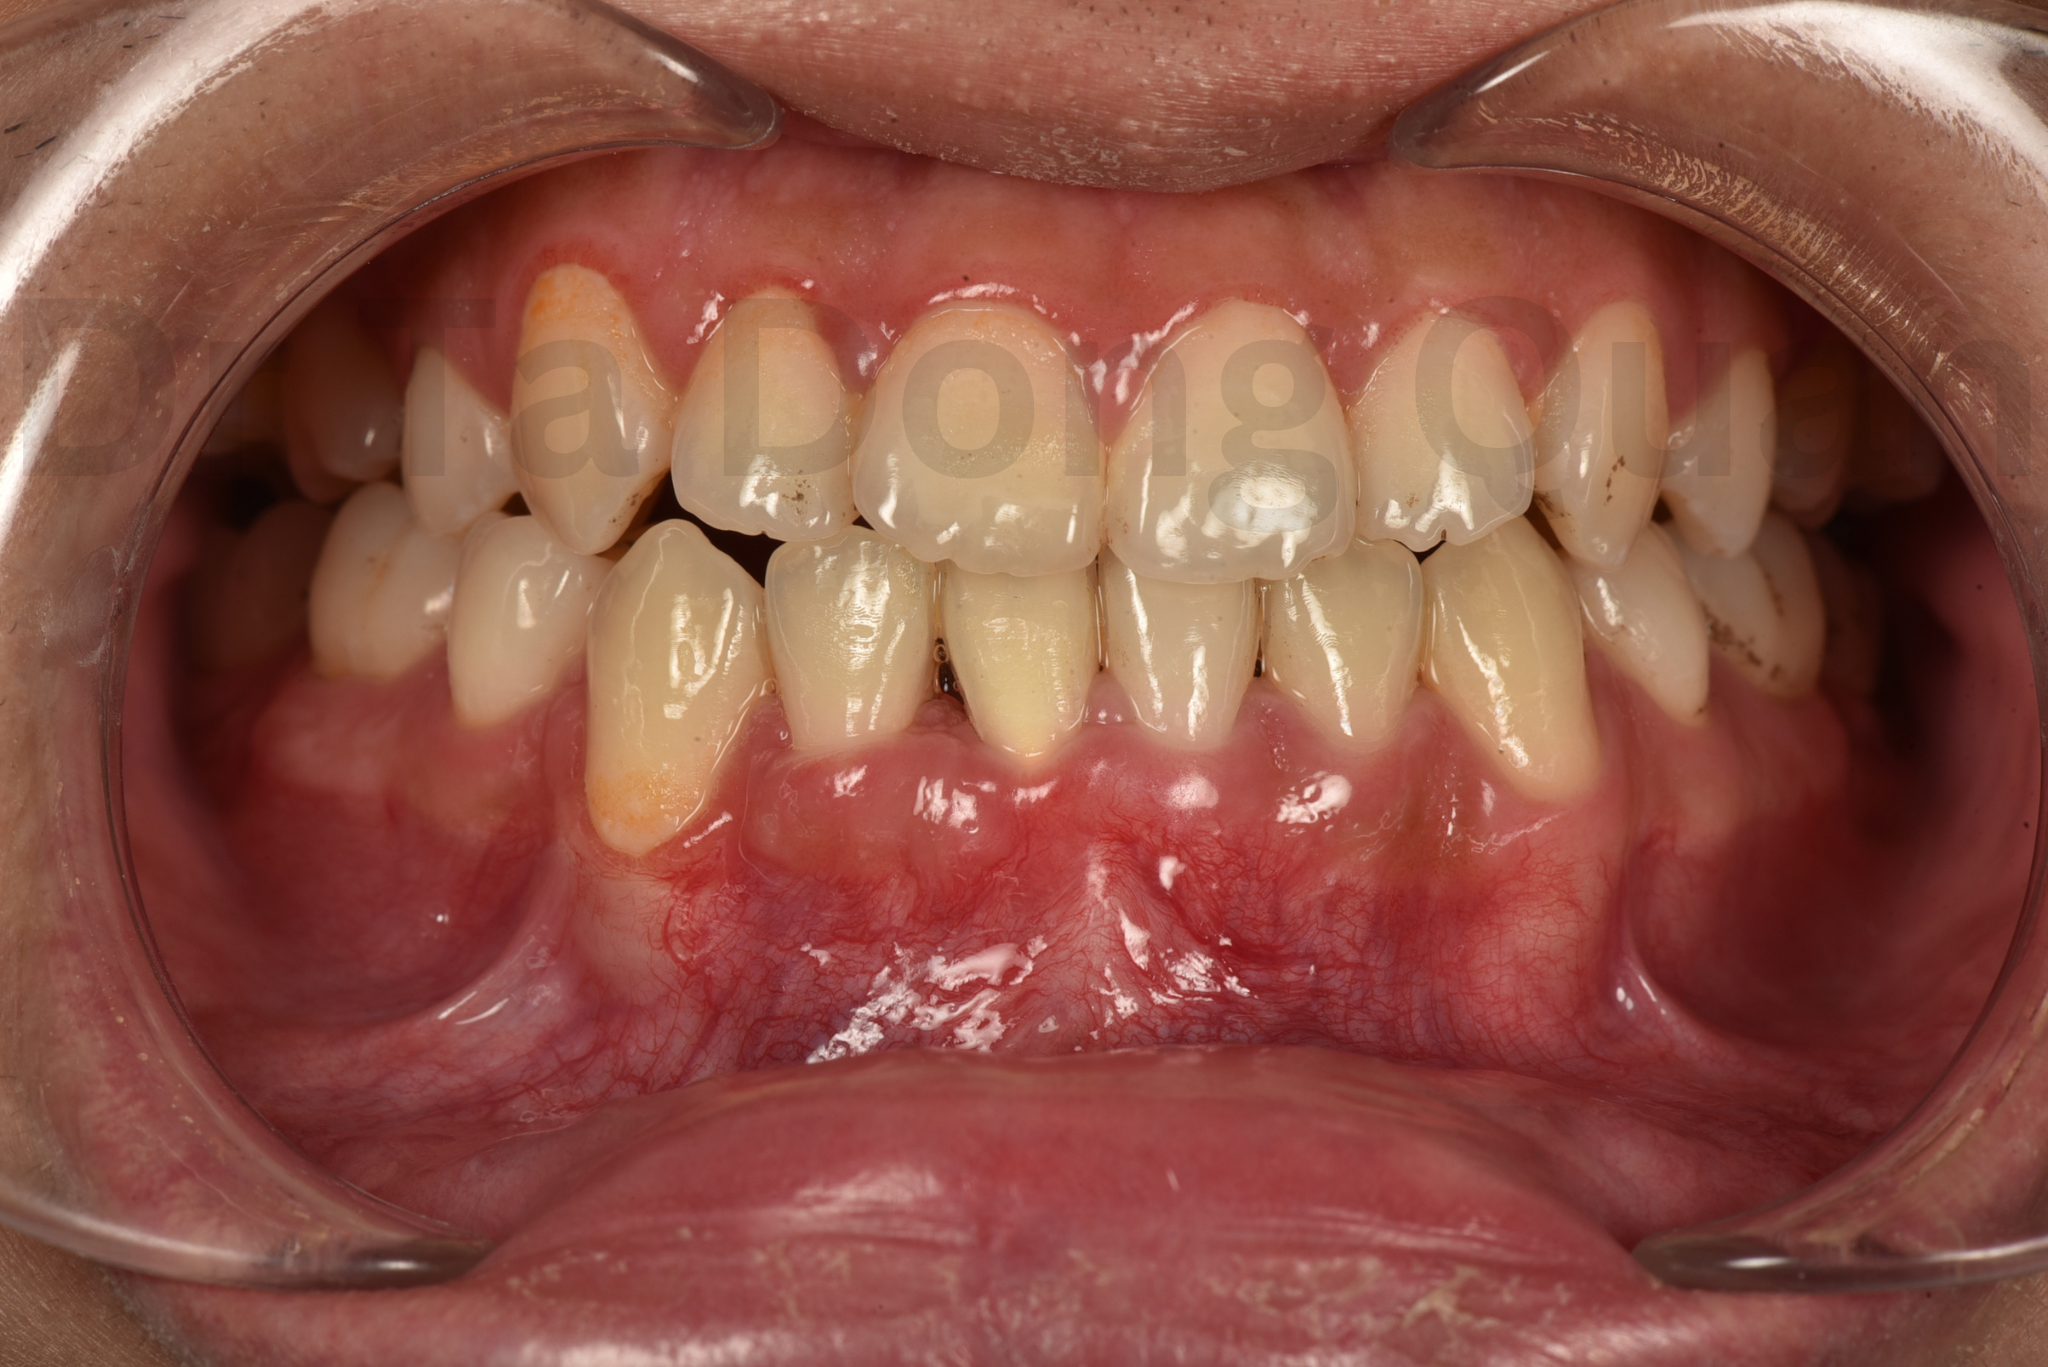

Hình ảnh trước và sau điều trị với kết quả thành công ngoạn mục đã được đăng trên tạp chí Lâm sàng của đại học Oxford (2024)